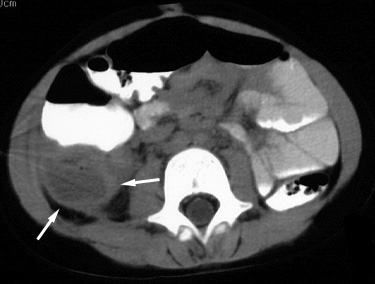

Figure 3. CT image at a lower level than Figure 2 shows a second appendicolith (large white arrow)within the fluid-filled dilated appendix. Note the similarity in appearance to the contrast-filled, dilated right distal ureter (small black arrow on the right; small black arrow on the left is the non-dilated distal left ureter). |

Figure 4. CT scan further caudal than Figure 3 shows the distal right ureter (black arrow) compressed by the adjacent dilated, fluid-filled appendix (A).B = urinary bladder. |

| Surgery revealed acute, non-perforated appendicitis. |